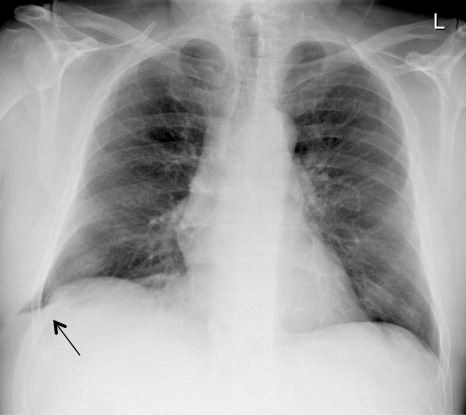

病例特点:胸部X线片显示左肺的基底部肺实质影延伸到胸廓左肋的外侧。胸部CT检查结果证明上述结论,左肺实质通过左下肋间外侧疝出,同时左侧胸腔伴有中等量胸腔积液。病人接受了肺疝手术,成功修复。